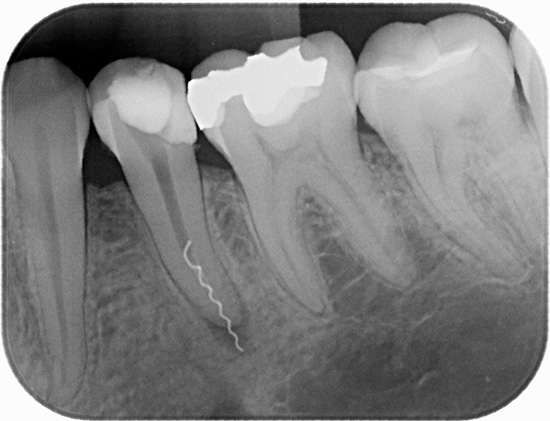

Lascando uma ferramenta em um canal

A quebra do canal de um instrumento dentário (geralmente um arquivo é quebrado) é uma das complicações mais desagradáveis do tratamento, tanto para o médico quanto para o paciente. Deixar a ferramenta no canal, se não for removida, está repleto de uma previsão desfavorável - extração de dente nos próximos anos.

Além disso, após o tratamento da pulpite, o dente pode ficar doente por muito tempo - até várias semanas (embora em alguns casos a dor possa desaparecer em termos normais, em apenas alguns dias, mas isso não significa que não há infecção na área do instrumento quebrado).

Se o arquivo quebrou no início do processamento do canal, isso não é tão assustador, pois o médico pode remover com relativa facilidade a parte quebrada com a ajuda de bicos ultrassônicos especiais. Se o arquivo se aproximar do final do canal, pode ser muito difícil obter o chip.

Nota

O uso de um microscópio odontológico ajuda muito nesse trabalho, mas nem todas as clínicas possuem esse equipamento. Portanto, às vezes, o médico tecnicamente não pode extrair um pedaço do arquivo do canal e é forçado a preenchê-lo como está - ou seja, com um fragmento dentro do canal (nem todo mundo está pronto para admitir seu erro, além da incapacidade de corrigi-lo,enviar o paciente para outra clínica).

A foto a seguir mostra um chip de ferramenta extraído do canal radicular:

No entanto, ainda é necessário obter o chip, porque a parte da ferramenta que permanece no canal bloqueia um determinado segmento da raiz e não permite que seu processamento seja concluído - portanto, um foco de infecção não tratado é formado, o que no futuro pode levar à extração dentária.